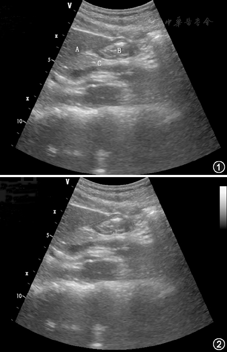

两组患者均采用同样的经鼻喂养管进行常规置管,胃管置入长度50~55 cm,妥善固定,营养液均使用同一型号的营养泵均匀持续滴入,滴注速度及量根据患者的耐受情况和胃残余量情况决定。观察组采取床旁超声监测胃残余量,如胃残余量≤200 ml,则每天监测1次(每天监测时间固定在上午10点)。患者取仰卧位(床头抬高30°),采用便携式彩色超声诊断仪探头频率3~5 MHz。切面选择胃窦单切面,即将超声探头置于患者剑突下方,以垂直腹部的角度,超声显影出胃窦大小(胃窦显影见图1,胃窦面积测量显影见图2),通过超声测量出胃窦面积,再通过胃窦面积与年龄的对比表得出胃残余量(表1)[4],当胃残余量>200 ml时,暂停肠内营养,则8 h后再次进行监测胃残余量,如胃残余量≤200 ml,维持原速度或根据患者营养需求增加速度。床旁超声由获取中国重症超声研究组规范化培训资质的两名护士对同一患者进行操作,如两人测量得出胃残余量的一致性>90%,则取平均值为最终结果,如一致性<90%,由获取重症超声培训师资的医生进行再次测量,得出的数据与更接近该数据的结果相加取平均值,以确保超声监测胃残余量的准确性;对照组采用注射器回抽法监测胃残余量,每8小时监测1次。当胃残余量≤200 ml,维持原速度或根据患者营养需求增加速度。胃残余量>200 ml,或≥50%的喂养量,停止肠内营养。